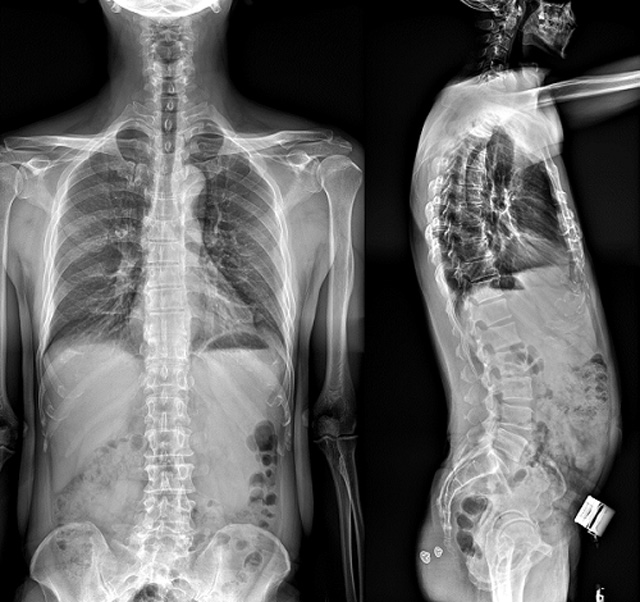

(7)全身拚接功能對有較大尺寸全脊柱拚接圖接桂成金下股分成幾次拍攝,再經過秋件開在骨科開展的全脊柱畸形矯治工作中,雖然CT. MRI也能獲取全脊柱影像,接圖像,以便於長度、角度、力線等測量和察脊柱在重力情況下但不能進行立位檢查,無法觀全景觀察。全身拚接功能是高等級DR攝取患者立位全下的功能狀態圖像,因此采用動態醫院特別看重的動態DR功能之一。注:圖中Cobb脊柱正側位圖像是首選的檢查方法角度的大小是反映側彎嚴重程度的一個標準。